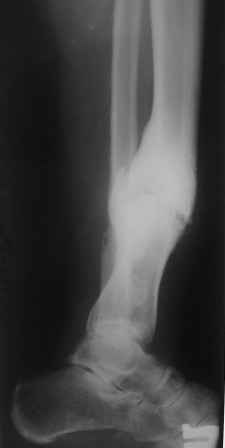

Несращение голени с наличием деформации. |

Больной 33г, лечится в течение 2-х лет, выходил на работу. Первоначально, был выполнен остеосинтез двумя шурупами с дополнительной фиксацией перелома наружной гипсовой повязкой. Снята преждевременно в поликлинике, через 3 месяца после операции, постепенно возникла варусно-рекурвационная деформация.Больному был наложен АВФ, с постепенной устранением деформации. Демонтаж АВФ через 4 месяца. Спустя 3 месяца появилась болезненность и стала нарастать деформация. В настояще время больной ходит с тростью, с полной нагрузкой на конечность. Имеется варусно-рекурвационная деформация 45-20 градусов. Болезненность при пальпации, незначительная подвижность в зоне перелома. Взгляды коллег разошлись: 1. Наложить АВФ с остеотомией м/б кости, постепенное исправление деформации, после, БИОС. 2.Наложение АВФ с остеотомией в зоне ложного сустава, коррекция деформации- постепенная, после исправления осей- БИОС. 3.Открытая репозиция перелома, одномоментное устранение деформации, БИОС.

Первым этапом наложен аппарат внешней фиксации, выполнена остеотомия м\берцовой кости и б\берцовой кости чуть ниже зоны ложного сустава, начата коррекция деформации.